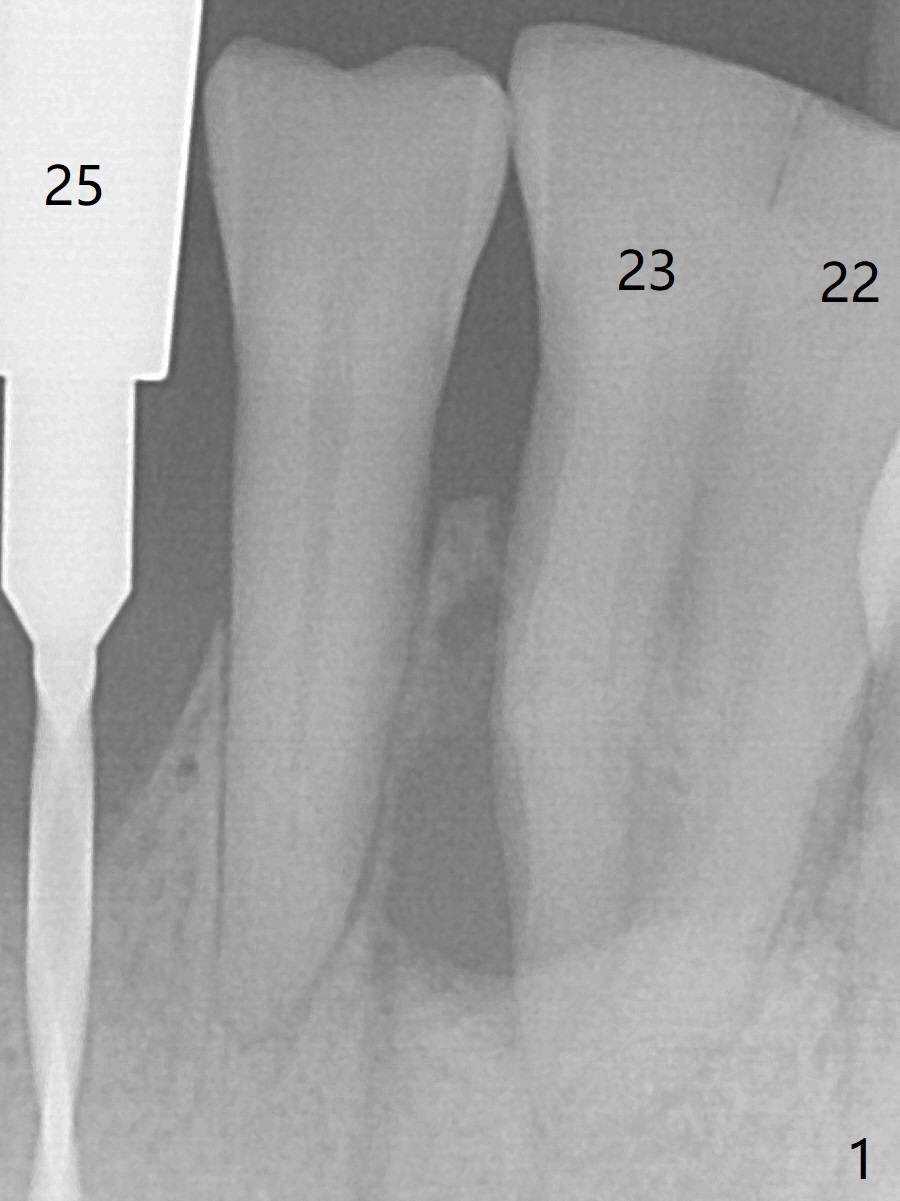

A 44-year-old woman will return for #22/23 (fusion) extraction and implant 2.5 months after one at #25 (Fig.1). If the mesiodistal width of the extraction socket(s) is not particularly wide, one implant will be placed. The tooth #22 seems to be buccally positioned (Fig.2 B). After extraction (Fig.3 black area), initiate osteotomy lingually (red line). Since the spongy bone is not wide buccolingually, a 3 mm implant appears to be appropriate (Fig.4).